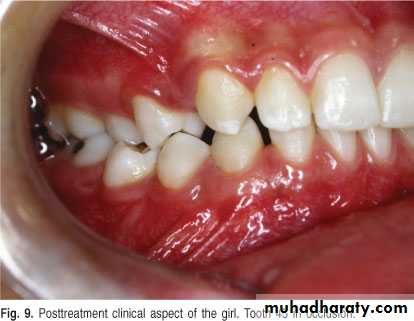

A 11-year-old female with swelling on the right side.

impacted canine